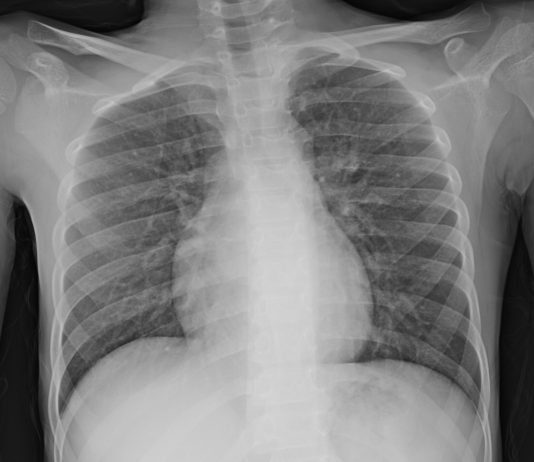

78-year-old patient with fever and cough for 1 week. pO2: 84 %.